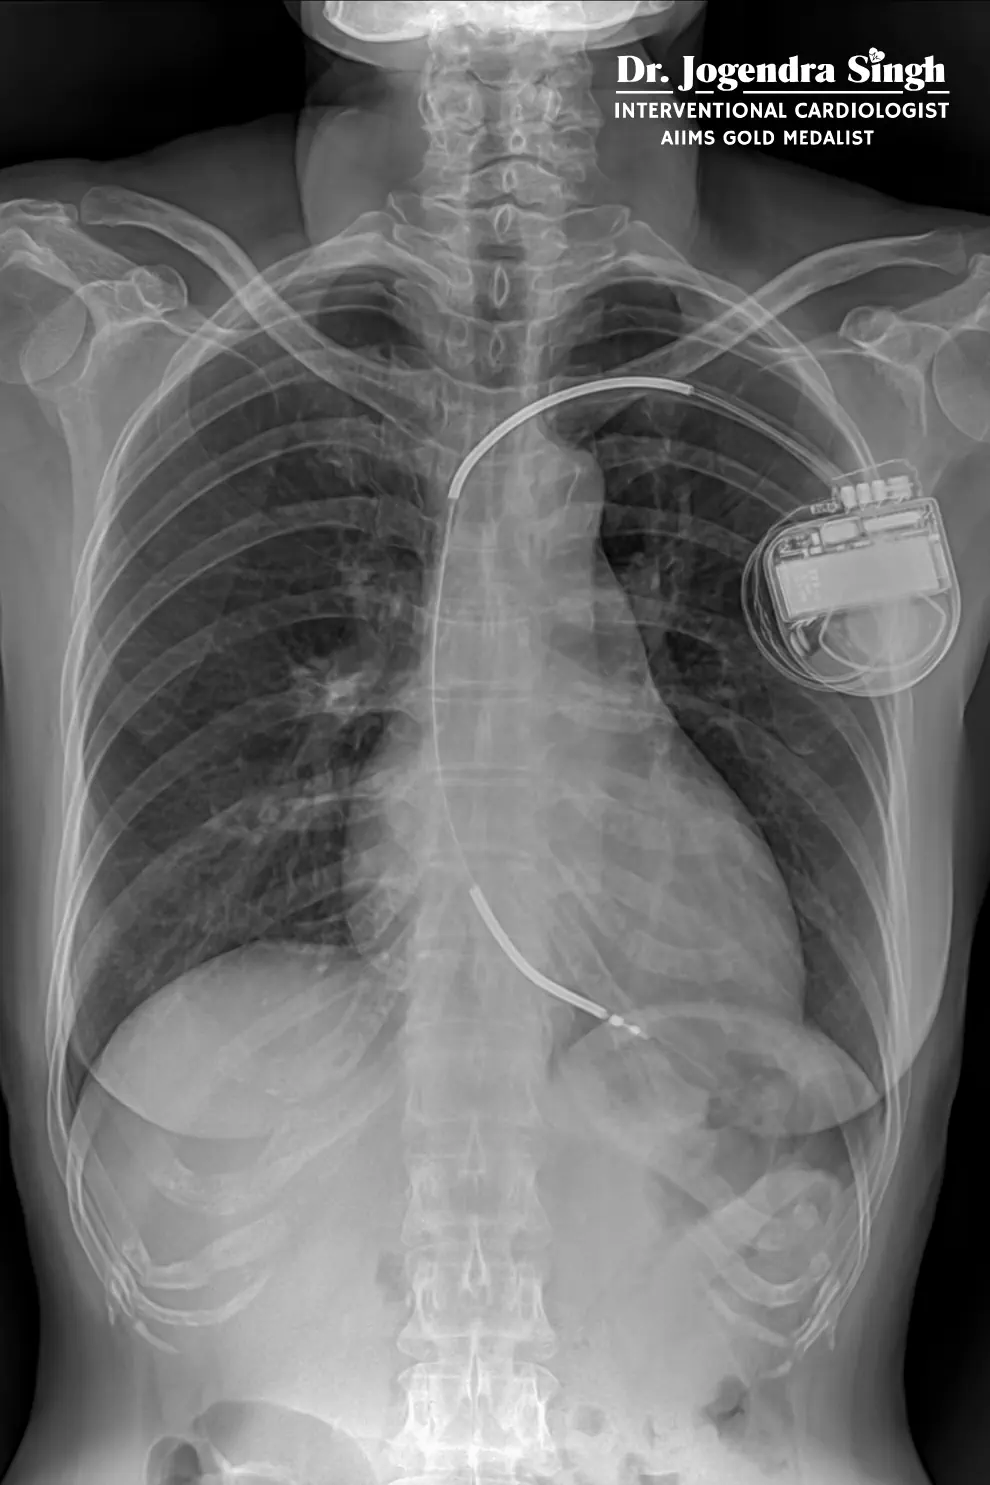

DEVICE IMPLANTATION

(Heart Rhythm Management)

Pacemaker Implantation

Single or dual-chamber pacemakers for slow heart rhythms (bradycardia).

AICD (Automatic Implantable Cardioverter Defibrillator)

A life-saving device for patients at risk of sudden cardiac death.

- Detects and treats dangerous arrhythmias automatically

CRT-P / CRT-D (Cardiac Resynchronization Therapy)

Devices for heart failure patients with electrical conduction abnormalities.

- Improves pumping efficiency

- Reduces symptoms

- Improves survival

Combo Device Implantation

Includes combined pacemaker + defibrillator capabilities for selected patients.